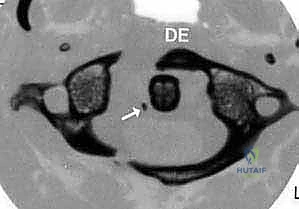

FIG 2 • A. An anterior atlantodental interval greater than 5 mm indicates likely injury to the transverse ligament and, in the setting of trauma, necessitates operative stabilization.

FIG 2 • B. An avulsion ( arrow ) of the transverse ligament from the ring of C1 indicates instability and may require arthrodesis of C1–2.